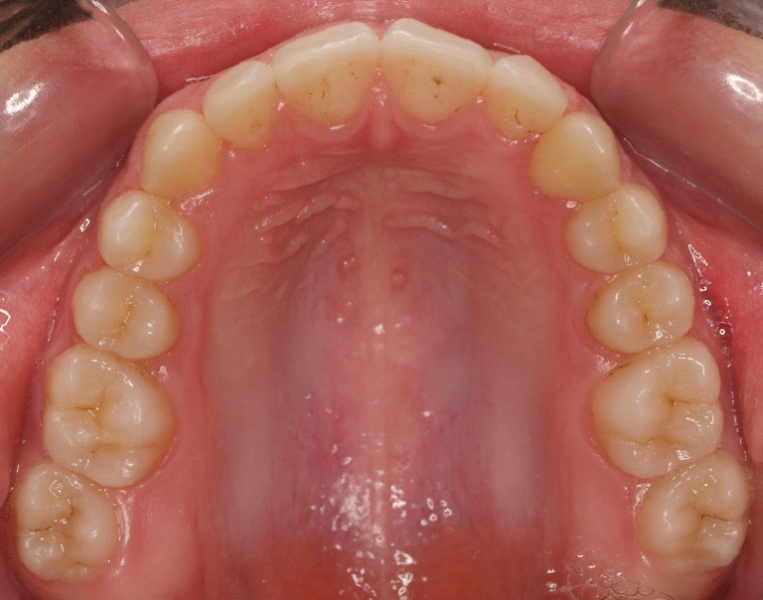

Clase II paciente 15 años

La paciente O.O. acude a nuestra consulta por:

– Canino 13 e incisivo lateral 42 en posición ectópica.

– Canino 23 incluido.

Con lo que decide realizarse un tratamiento de ortodoncia de duración de 24 meses con brackets damon Q.

CASO COMPLETO: